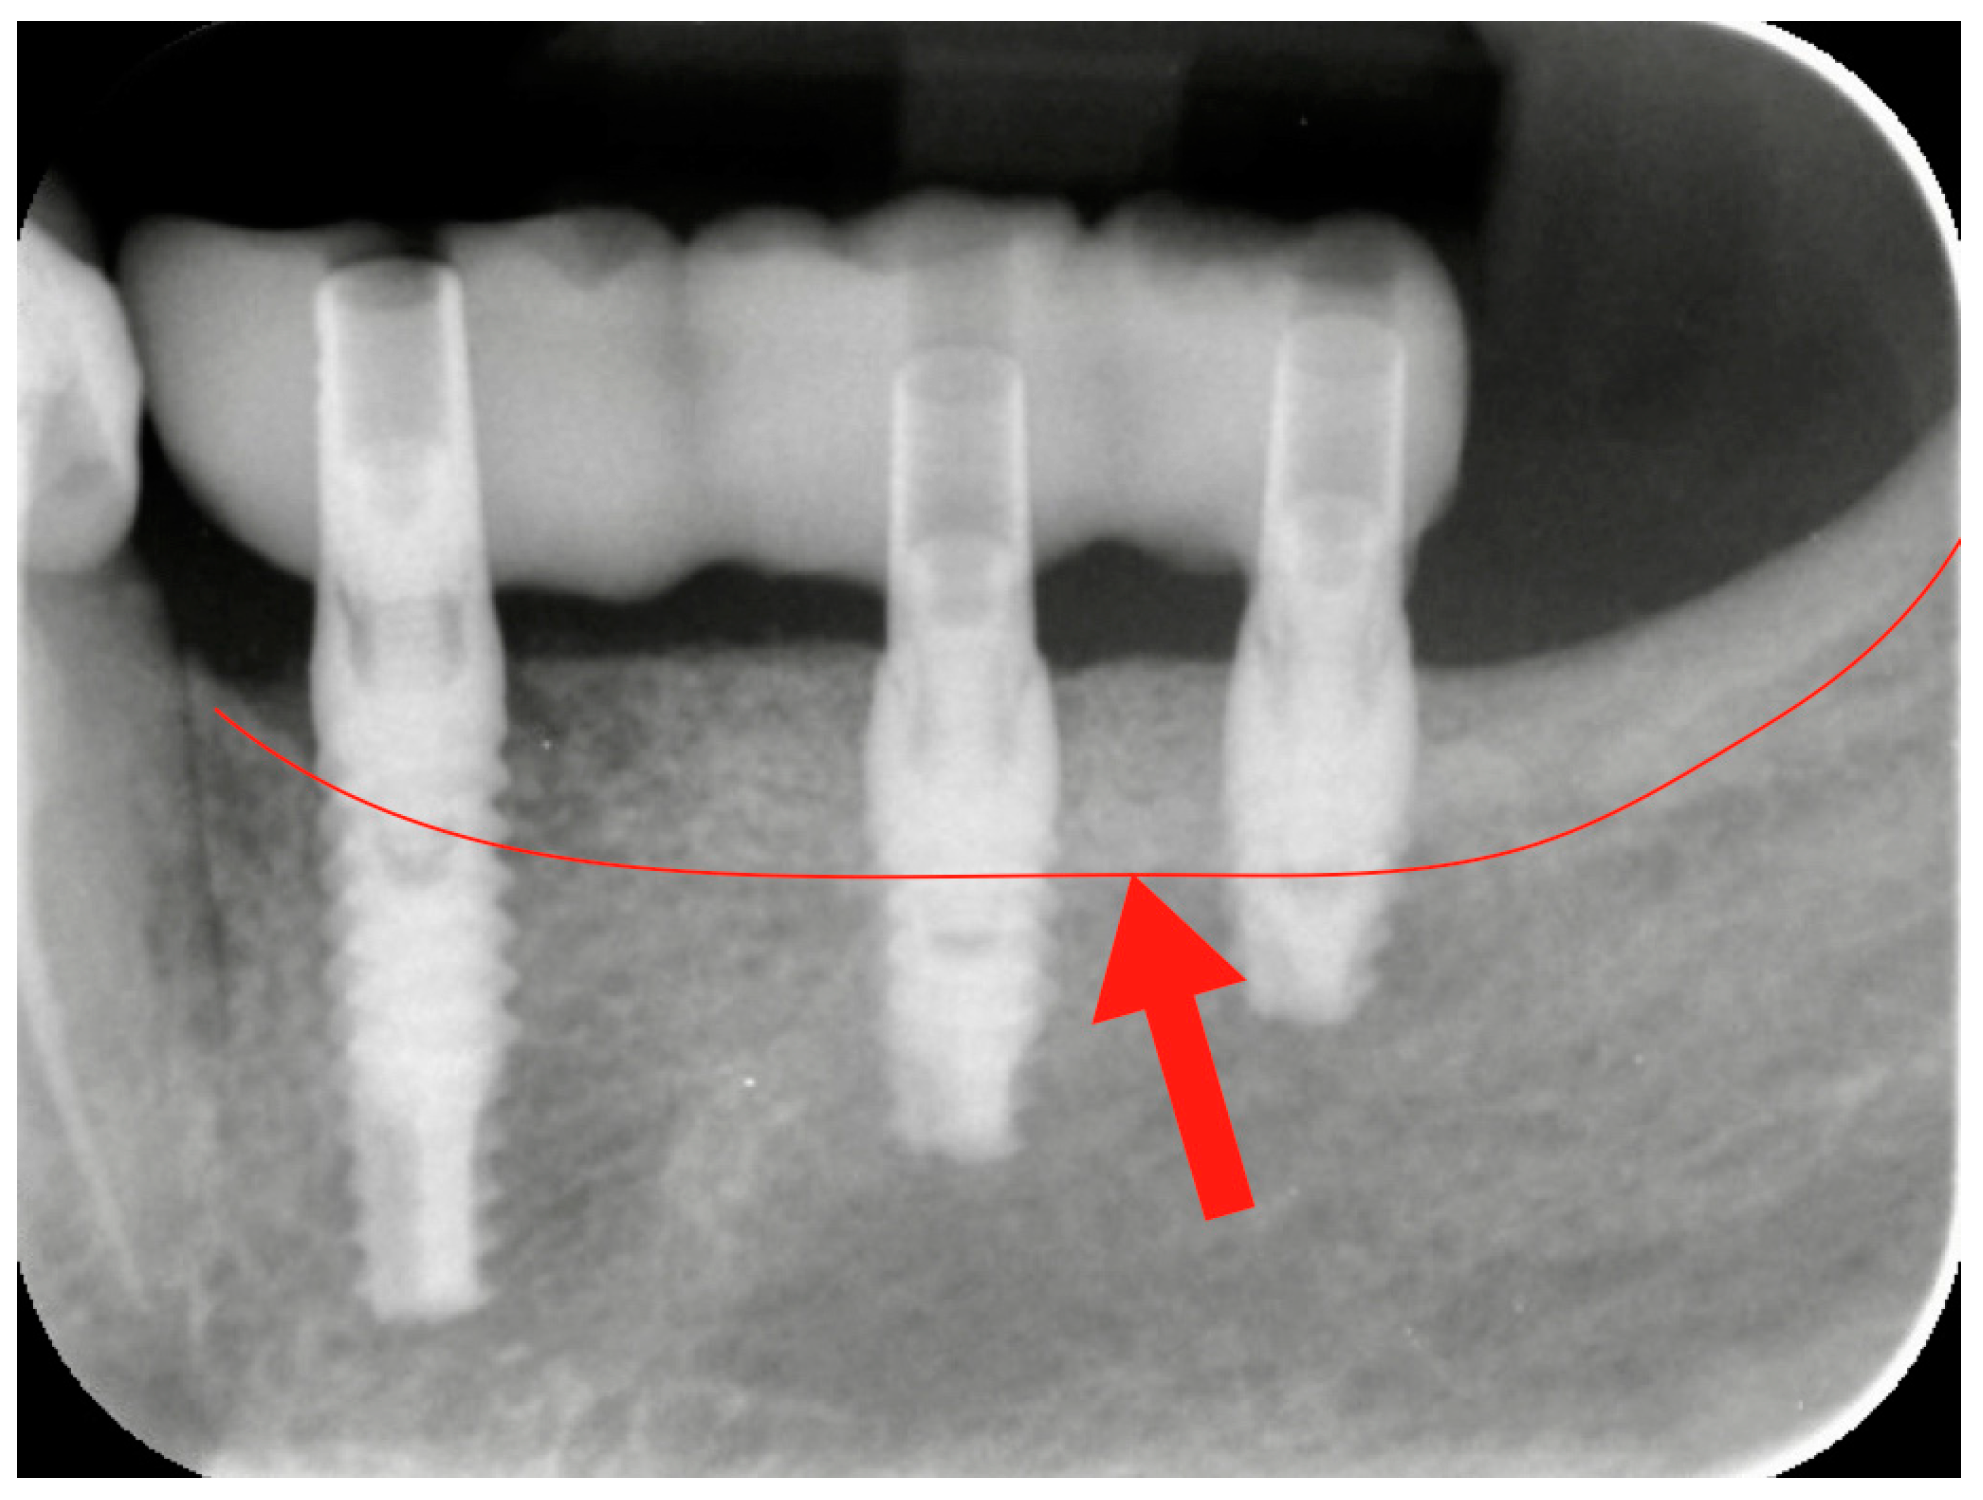

2.4. Prosthetic Loading

After three months, the healing abutment was replaced with a permanent abutment, and acrylic resin provisional restorations were placed. They were left in situ for two months, before being replaced by definitive zirconia–ceramic restorations. A radiographic follow-up was performed before prosthetic finalization for all cases to verify the conditions of hard peri-implant tissues (Figure 4).

Figure 4. Radiographic check-up after the provisional resin restoration placement. The red line and the red arrow show the bone level before the vertical bone augmentation. The bone portion above the red line represents the amount of the vertical regeneration.